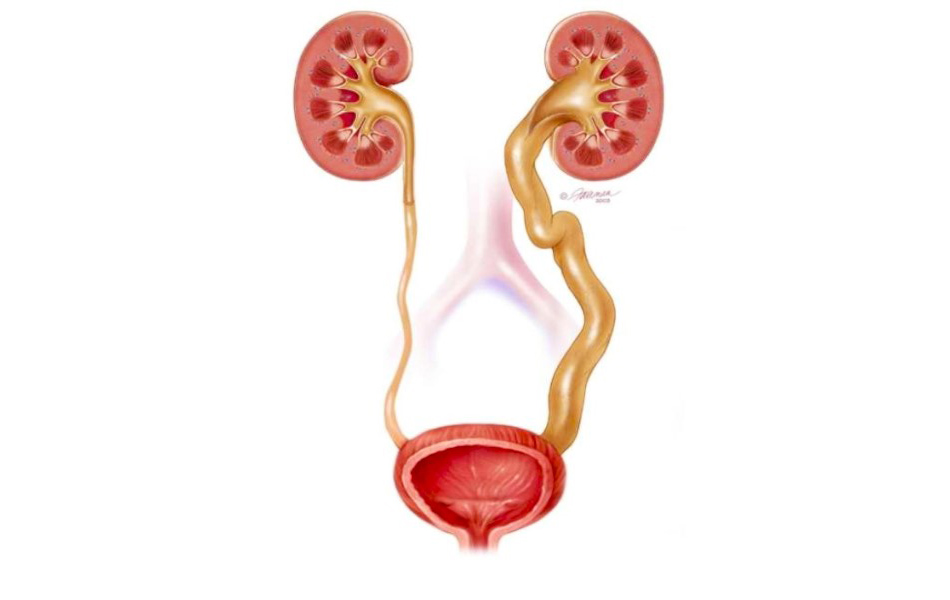

Рефлюксирующий мегауретер: Визуализация и медицинские изображения

Раздел: Фотопуть к знанию